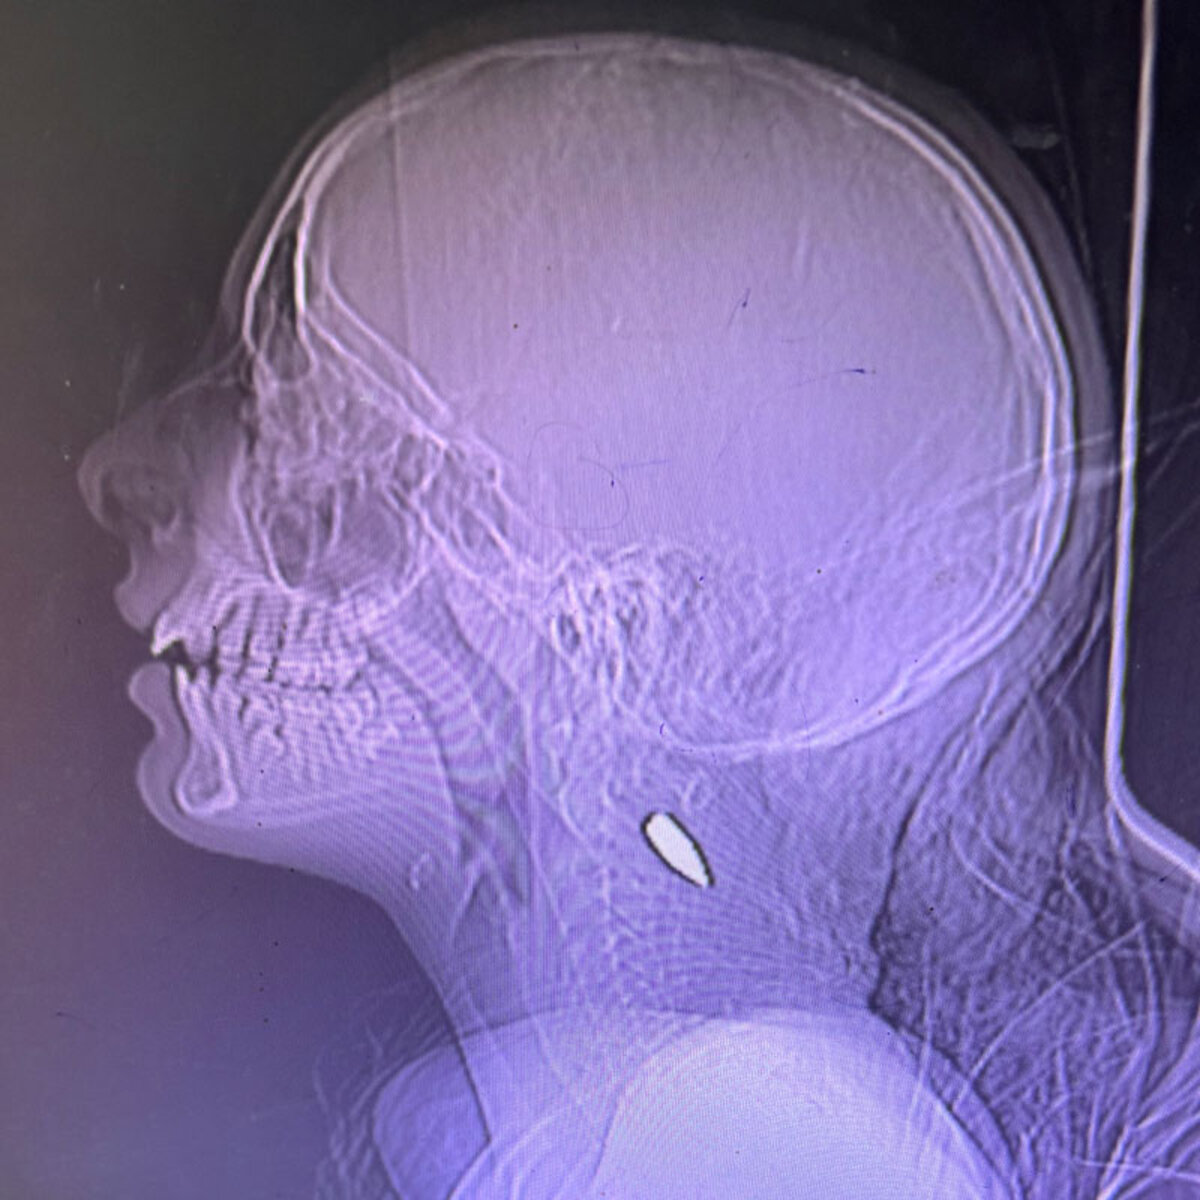

Agrandir l'image : Illustration 1

Agrandir l'image : Illustration 2

Agrandir l'image : Illustration 3

Ces radiographies montrant des enfants de Gaza avec des balles dans le cou ou la tête ont été partagées par le Dr Mimi Syed, qui a travaillé à Khan Younis du 8 août au 5 septembre. Elle a expliqué : « J'ai pris en charge de nombreux jeunes patients, pour la plupart âgés de moins de 12 ans, atteints d'une balle dans la tête ou dans la poitrine, sur le côté gauche. En général, il s'agissait d'une seule balle. Les enfants arrivaient soit déjà morts, soit dans un état critique, et mouraient peu après leur arrivée. »